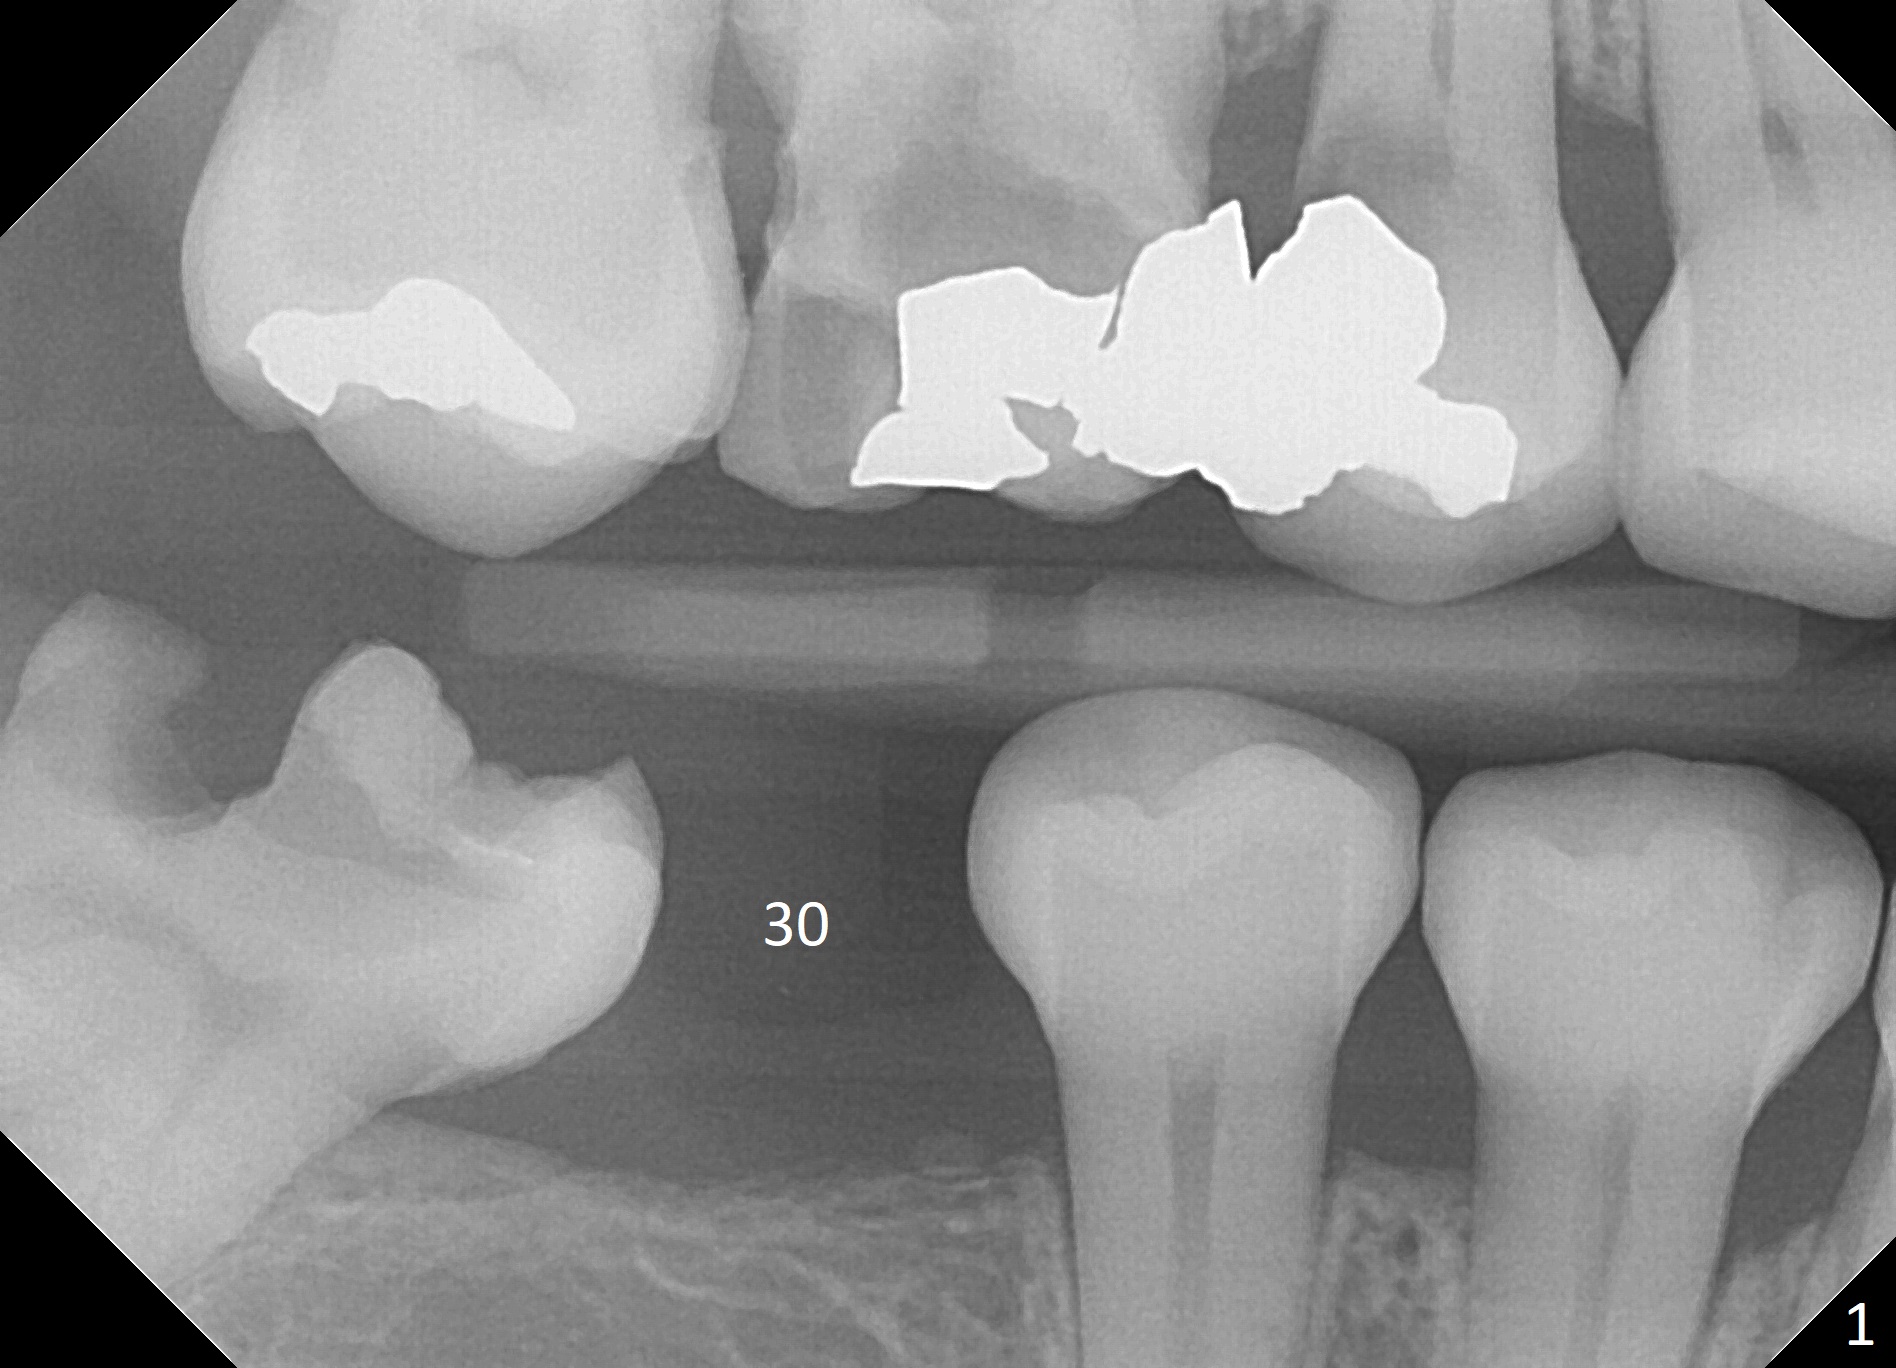

A 54-year-old woman has poor dentition (Fig.1). The teeth #3 and 4 have had composite with crowns and/or RCT pending, while IRM has been placed at #31. Since the temporary restoration is breaking down at #31, composite will be placed with Isolite. Crown prep will be also done at #31, especially mesially, and splinted provisional will be fabricated at #30 and 31 immediate following #30 implant placement. If the ridge at #30 is narrow, ridge reduction will be done with possible use of a 3.5x10 mm or 8.5 mm 1-piece implant (Tatum or IS, Fig.2). Prepare implant positioner. Under prepare the site because of low density bone.